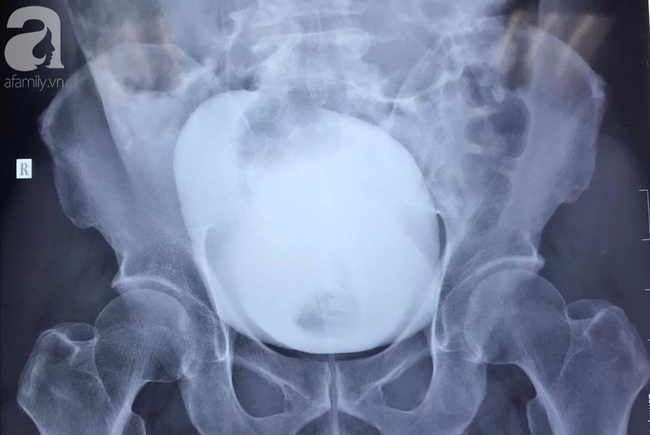

![]() |

| Ảnh chụp X-quang cho thấy bàng quang bệnh nhân bị vỡ (có vùng đọng màu trắng ở giữa. (Ảnh: Tổ quốc) |

Theo báo Tổ quốc, bác sĩ Trần Lê Duy Anh, khoa Ngoại niệu – Ghép thận, người tiếp nhận điều trị trường hợp trên chia sẻ, bệnh nhân nhập viện vào lúc 22h30 ngày 13/1 trong tình trạng đau bụng nhiều vùng hạ vị, gồng cứng, chẩn đoán theo dõi bàng quang/chấn thương bụng kín. Kết quả siêu âm bụng, CT bụng cản quang khẩn ghi nhận vỡ bàng quang trong phúc mạc.

Người đàn ông bị trượt ngã vỡ bàng quang sau đó được mổ cấp cứu. Các bác sĩ xác định bệnh nhân vỡ bàng quang 7cm, nhiều máu trong ổ bụng. Sau mổ, tình trạng bệnh nhân ổn định và hiện đang tiếp tục được theo dõi.